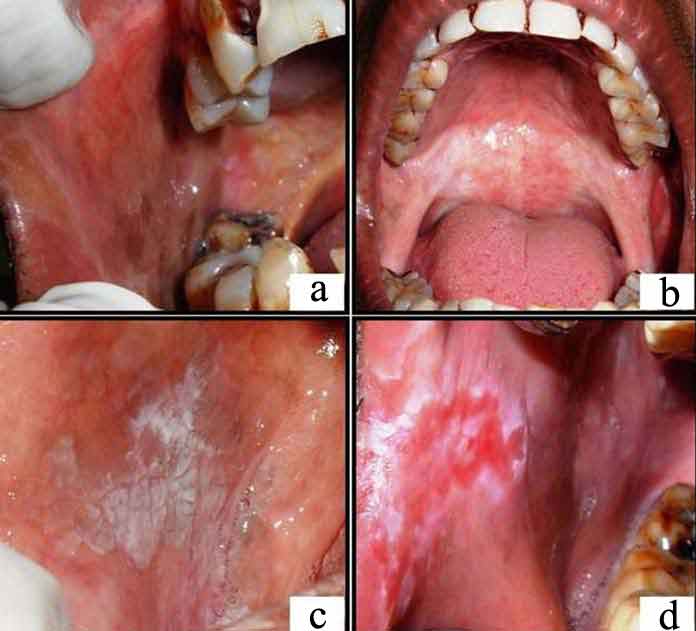

(a) Shows blanching and presence of fibrous bands in right buccal mucosa; (b) Shows blanching of soft palate; (c) Shows homogenous oral leukoplakia on right buccal mucosa; (d) Shows non-homogenous oral leukoplakia on right commissure and buccal mucosa.